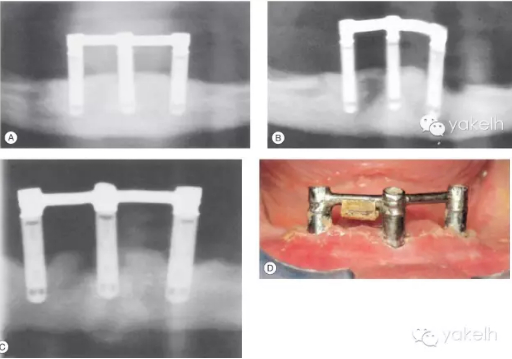

72歲女性患者,行下頜3顆種植體支持覆蓋義齒修復(fù)(圖.15A)。5年復(fù)查發(fā)現(xiàn)左側(cè)遠(yuǎn)中1顆種植體發(fā)生了種植體周圍炎(圖.15B)。在隨后的5年中,種植體周圍炎進(jìn)一步發(fā)展,在種植體周圍形成了彈坑樣的骨缺損(圖.15C)。

由于隨著患者年紀(jì)變大,身體越來越虛弱,而無法保持種植體周圍以及義齒下端的口腔衛(wèi)生,從而導(dǎo)致種植體周圍炎的易感性進(jìn)一步增加(圖.15D)。

圖.15 (A~C)這3張放射片間隔5年拍攝,顯示種植體周圍骨組織不斷喪失。 (D)口內(nèi)照顯示口腔衛(wèi)生差,種植體周圍軟組織存在炎癥。